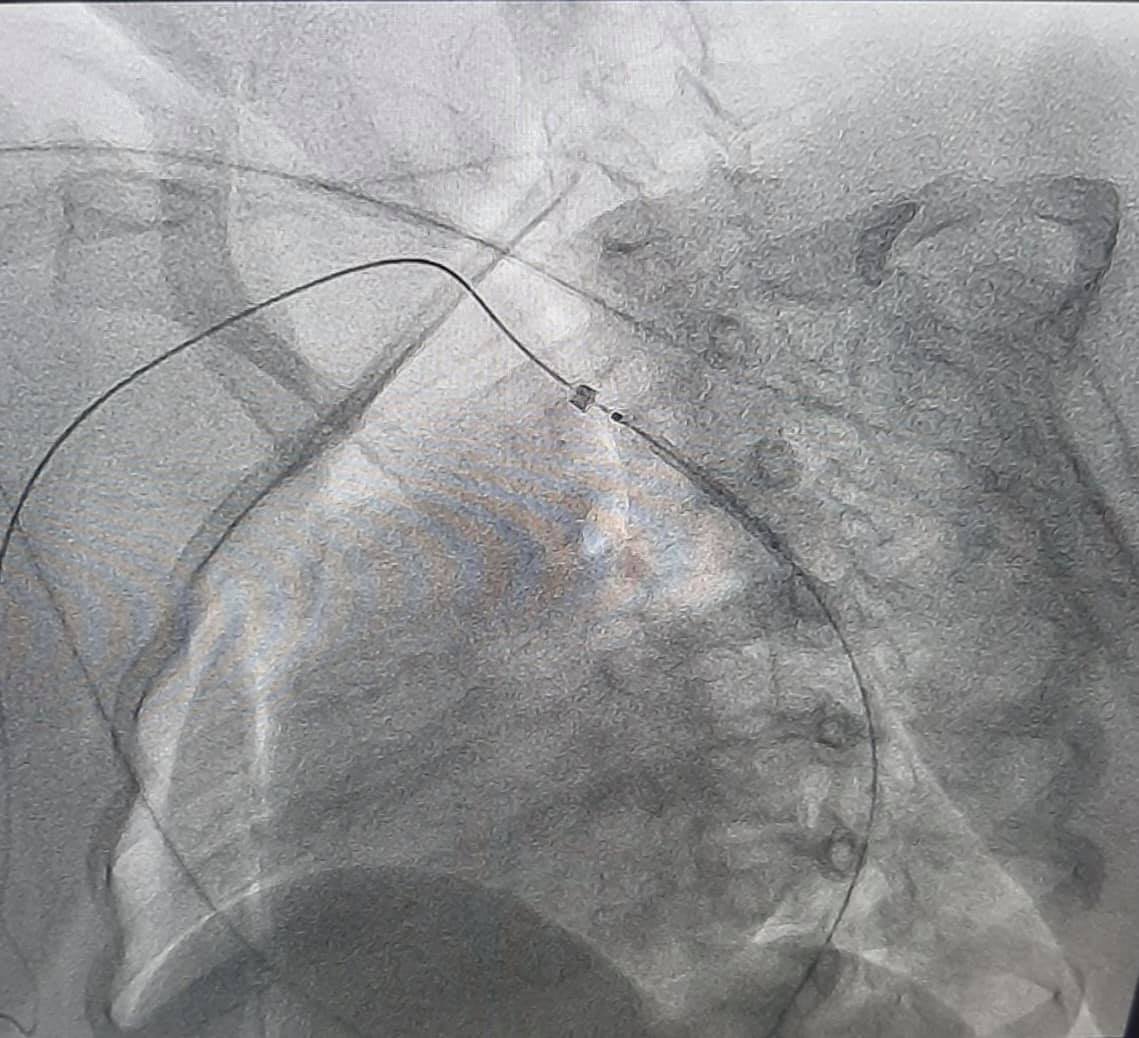

Во время обследования у девочки нашли врожденный порок сердца — коарктацию аорты. Это состояние, при котором имеется сужение просвета аорты, вследствие чего развивается повышенное давление в верхней половине тела. С помощью современных технологий на основе результатов обследования была проведена виртуальная реконструкция анатомии аорты и её ветвей, что помогло медикам выбрать наиболее современную и малотравматическую тактику дальнейшего лечения.

Врожденный порок сосуда убрали с помощью процедуры — установления стента в просвет сосуда.